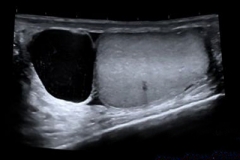

硬结,或是囊肿,都是容易发生在附睾部位的疾病,而附睾囊肿不同于实性坚硬的硬结,它是一种囊性的肿块,其中含有液体和精子等内容。附睾囊肿最常发生在头部,所以门...

附睾囊肿为青壮年的高发病,也称为精液囊肿。附睾囊肿好发于头部,主要表现为增大肿块,严重者会导致男性不育,所以在治疗上还需重视。该怎么治疗附睾囊肿呢?

附睾囊肿是青壮年男性中较多发的一种疾病,多位于附睾头部,又称为精液囊肿。附睾囊肿对男性的生育有着极为重要的影响。中医认为,附睾囊肿是下焦湿热、经络受损、气...

附睾囊肿的患者高发于青壮年男性,也被称之为精液囊肿。其病发的常见部位为附睾头部,主要表现为增大肿块。附睾囊肿不但会引发多种并发症,同时还会影响男性生育。而当前的...

附睾囊肿是青壮年(20~40岁)男性的高发病,又称为精液囊肿。附睾囊肿发生的常见部位是附睾头部,在附睾处有增大的肿块。可能会导致男性出现性功能障碍,从而降低生育...